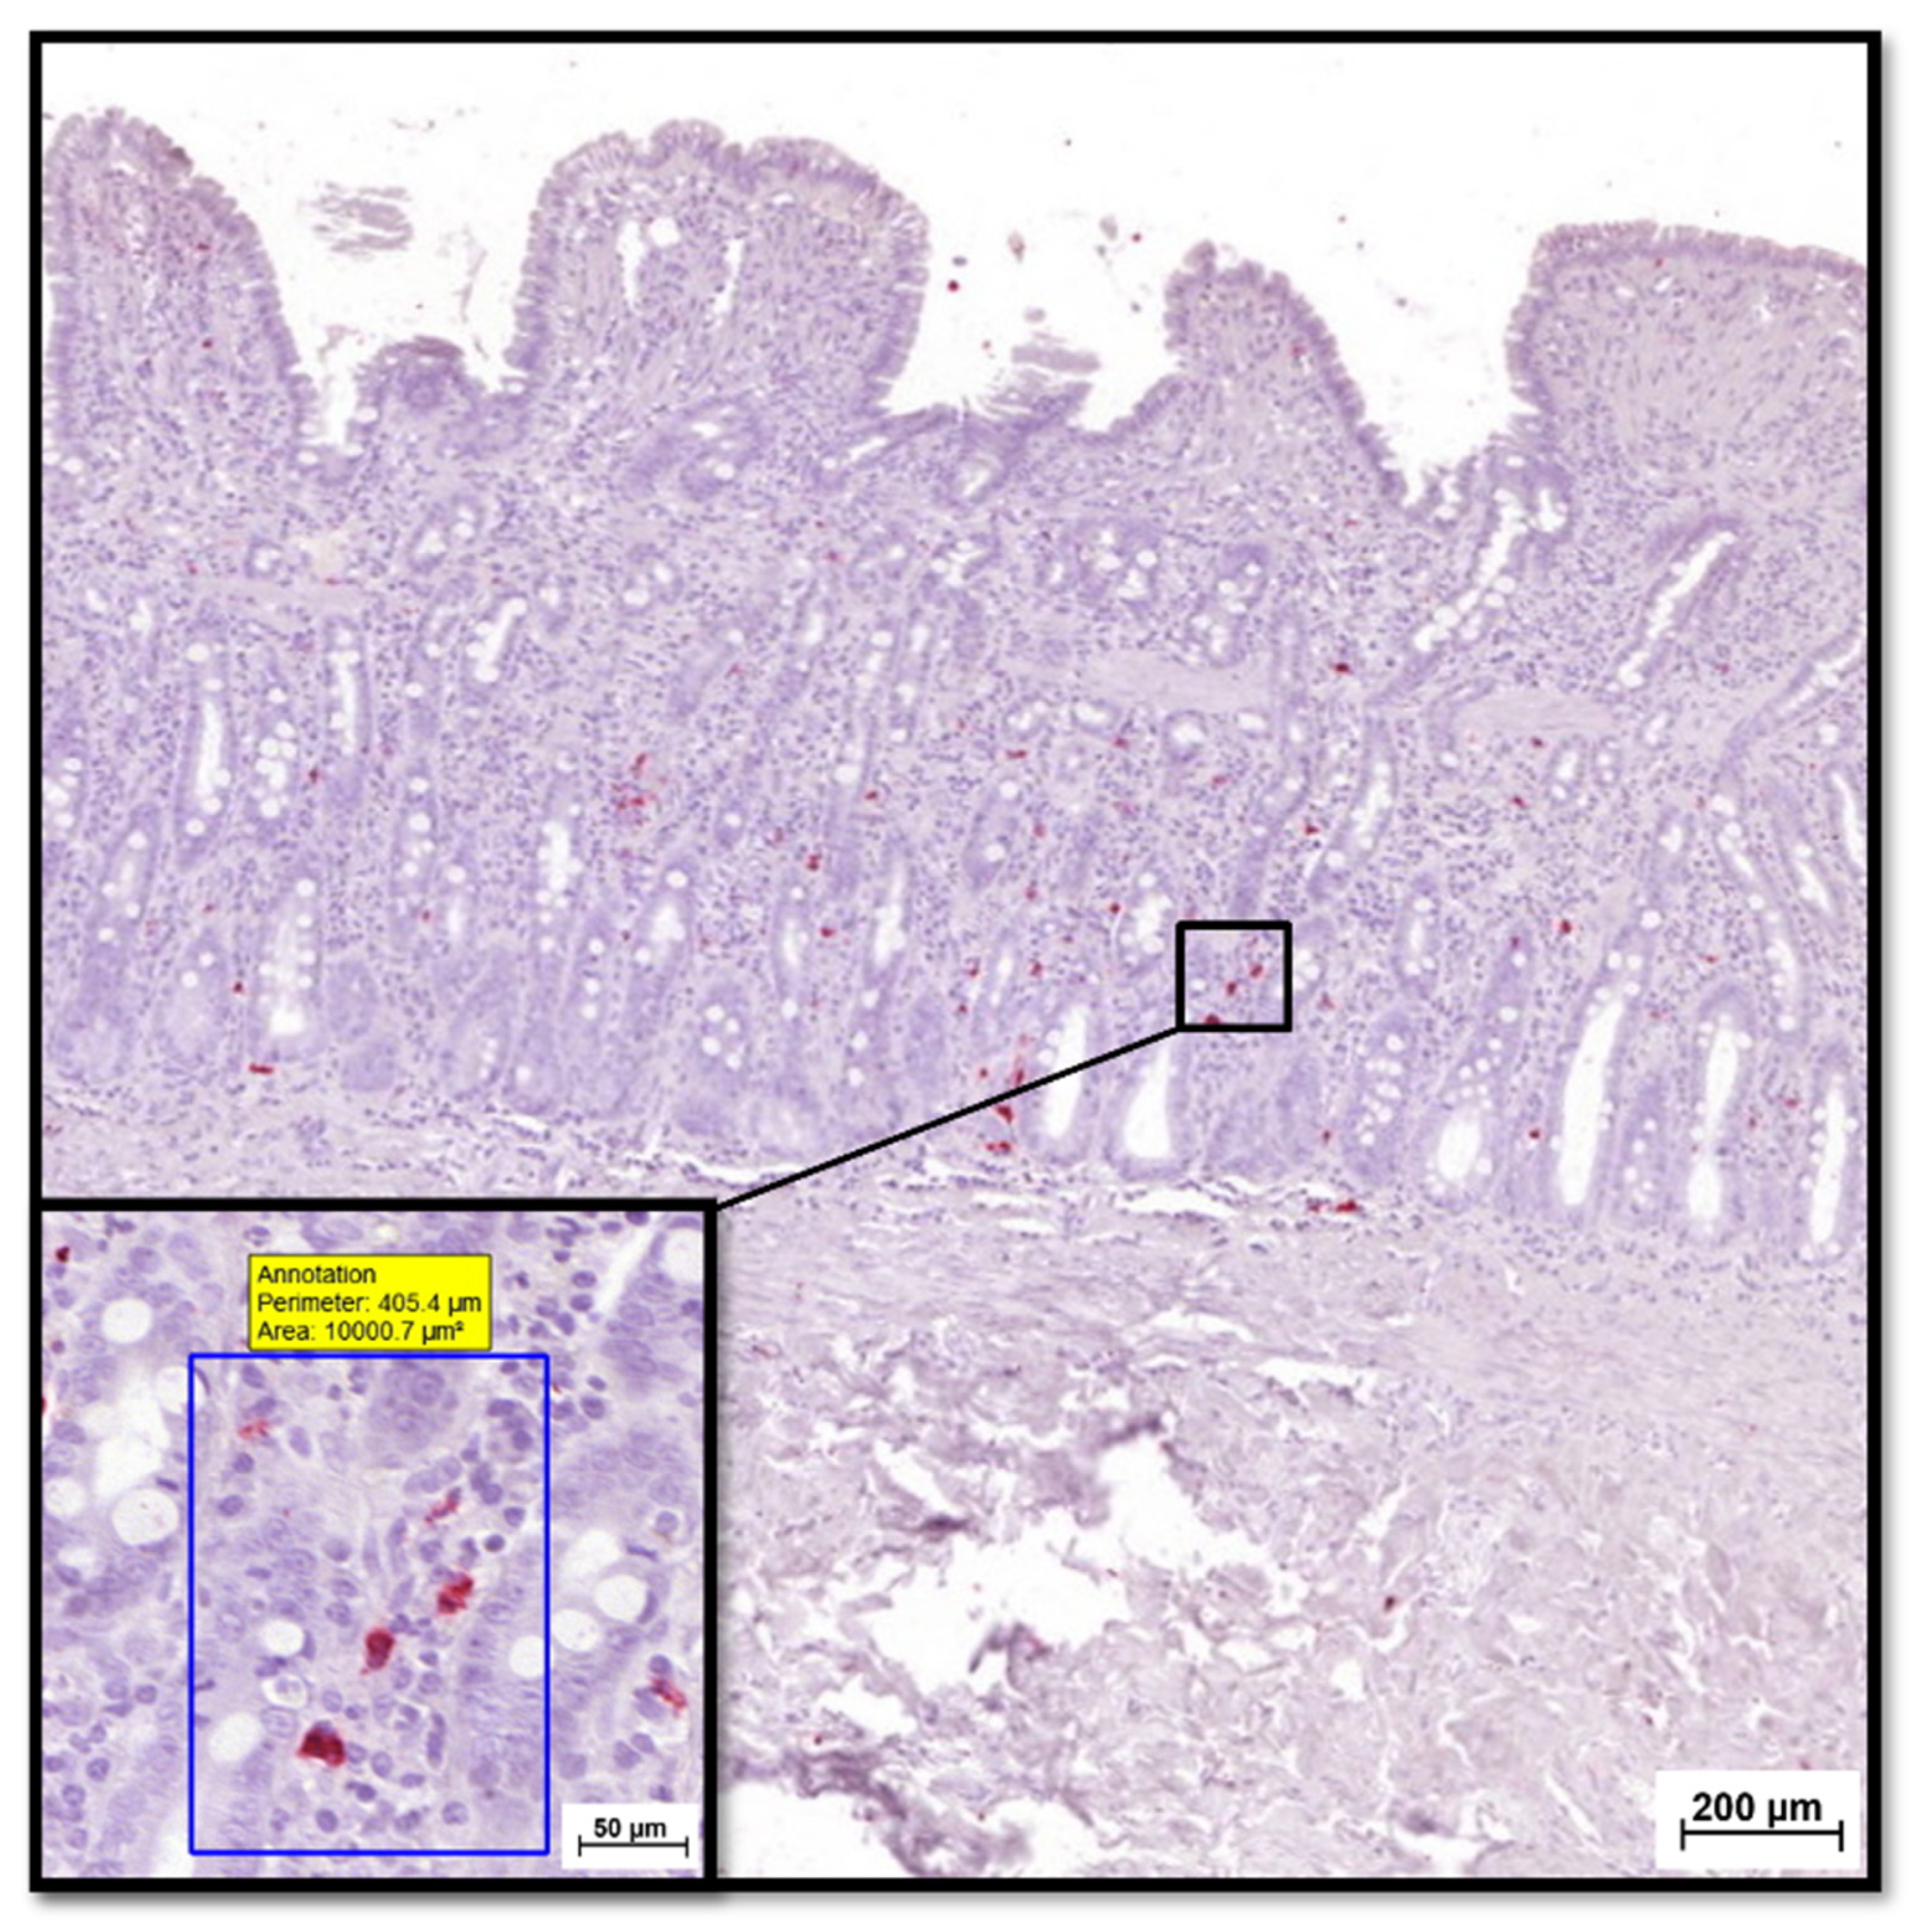

2.5. S100A8/A9 and S100A12 IHC Analysis of Feline GI Tissue Biopsies

- Heilmann, R.M.; Nestler, J.; Schwarz, J.; Grützner, N.; Ambrus, A.; Seeger, J.; Suchodolski, J.S.; Steiner, J.M.; Gurtner, C. Mucosal expression of S100A12 (calgranulin C) and S100A8/A9 (calprotectin) and correlation with serum and fecal concentrations in dogs with chronic inflammatory enteropathy. Vet. Immunol. Immunopathol. 2019, 211, 64–74. [Google Scholar] [CrossRef]